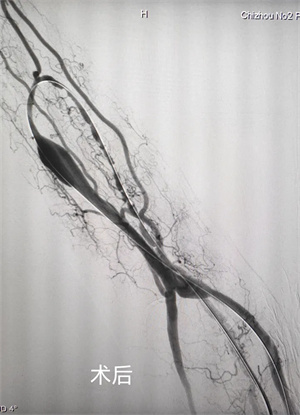

日前,我院普外二科与血透中心紧密协作,成功开展“DSA引导下动静脉瘘狭窄球囊扩张成形术(PTA)”,为内瘘狭窄患者带来了更精准、更微创、更高效的治疗新选择。接受该手术的患者术后内瘘震颤即刻恢复,达到理想透析血流量要求,充分满足了透析治疗的需求。

PTA技术通过DSA精准介入定位,使球囊扩张狭窄血管段,无需开刀即可恢复通路血流,该技术具有创伤小、恢复快、可重复操作的显著优势,不仅能迅速解决当前狭窄问题,更能最大程度保护患者血管资源,显著延长动静脉瘘的使用寿命,有效避免反复开放手术带来的痛苦与风险。